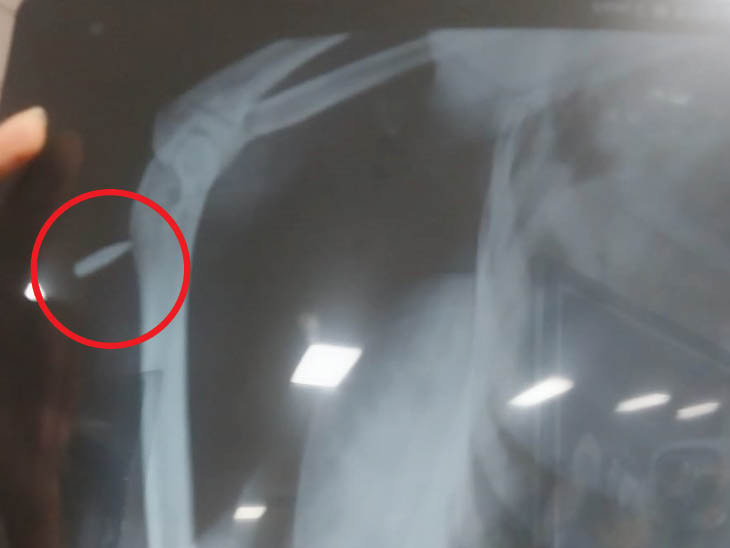

जोधपुर के एमडीएम अस्पताल में घायल छात्रा रेणू विश्नोई की कोहनी का एक्स-रे, जिसमें गोली साफ दिखाई दे रही है।

पुलिस ने दाबा किया कि किसी गाड़ी के टायर से उछले पत्थर के कारण छात्रा चोटिल हुई है। हालांकि जब हॉस्पिटल में घायल छात्रा का एक्सरे करवाया तो उसमें गोली नजर आई। इसके बाद पुलिस हरकत में आई और मौके से सबूत जुटाए। घटना मानजी का हत्था इलाके की है।

चाय की दुकान के पास खड़ी कार के बोनट से गोली टकराई थी, जिसके कारण बोनट पर निशान हो गया। (लाल घेरे में गोली का निशान)